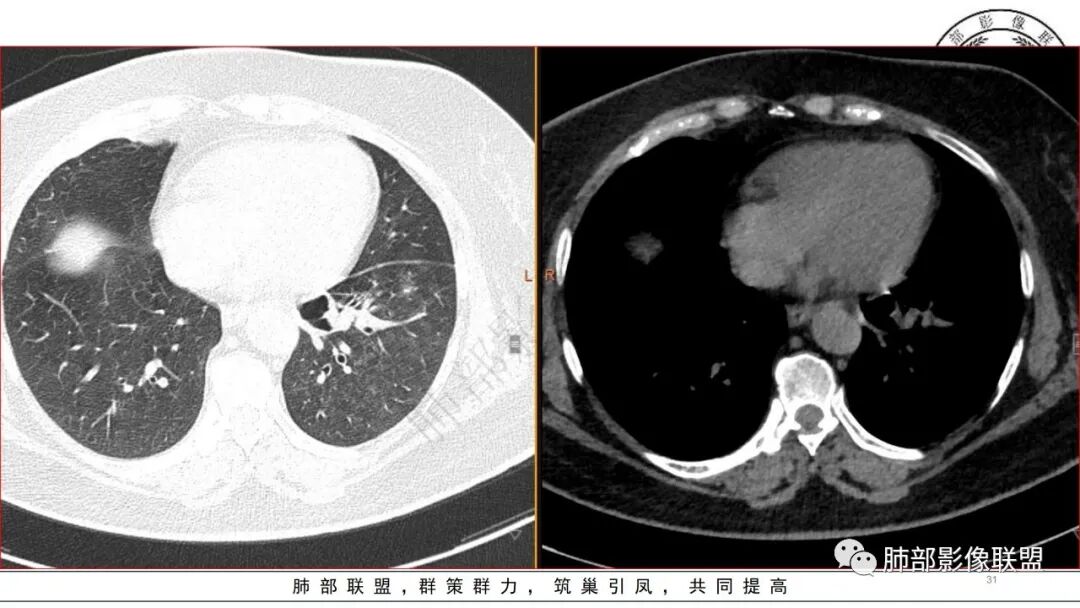

发一个金葡的对比一下

我这个也是金葡菌

3.金黄色葡萄球菌临床中毒症状明显,常寒颤高热起病,血源性感染者常有皮肤脓肿、伤口感染、蜂窝织炎、化脓性骨髓炎等等。病情变化快,影像进展迅速,短期内(如一两天内)迅速出现的有张力的菲薄气囊影,或多发成串分布的,尤具特征性!较之其他感染,短期内易出现脓胸。本例上述特征似乎不明显。

金葡应该也是血源性来源,因此也存在鉴别,区别在肝脏,肺克的血播是肝脏来源,金葡的血播可以各种来源,但是一般不会是肝脏来源,具体来说,金葡的SPE观察不那么典型,金葡可以形成更大的实变,肺克少一些,金葡的特征应该还是气囊,壁的张力更高,更薄,SPE似乎不明显,临床上皮肤软组织脓肿的有无,这个特征肺克应该不具有,但肺克一般有肝脓肿,没有的少见。